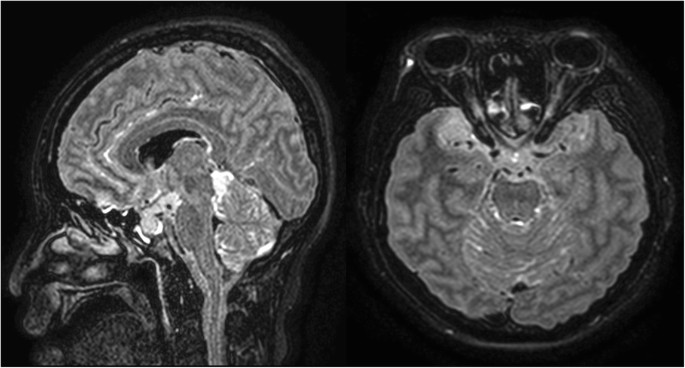

Brain MRI performed 3 months before the visit showed extension of the tumour from the brainstem to the upper thoracic spinal cord and another lesion at the right temporal pole.

Figure 1 on presentation, she was drowsy and vital signs were as follows: blood pressure, 125/65 mmHg; body temperature, 36.4 °C; pulse rate, 100 per minute; respiratory rate, 19/min. The emergency medical faculty immediately gave her intravenous LEV 1000 mg; however, there was one more generalised tonic-clonic seizure without mental recovery. Video-EEG monitoring was initiated 2 h after the end of LEV loading; at that time, she started to show choreoathetoid movements in her face and bilateral limbs (see Additional file 1), but no epileptiform discharges were noted on concomitant electroencephalography (EEG) as seen in Fig. 2. Laboratory findings including complete blood counts, electrolytes, blood urea nitrogen, creatinine, and arterial ammonia levels were normal. Review of her medical history revealed that she had been treated with solifenacin, esomeprazole, baclofen, and escitalopram for more than 3 months. She was not on concomitant drugs such as dopamine receptor blockers or antipsychotic agents. Considering the temporal relationship between the onset of involuntary movements and administration of LEV, further treatment with LEV was withheld. Chorea movement continued for about 30 min. She could communicate with her caregiver and physician until the end. After administration of 4 mg of lorazepam and 1200 mg of phenytoin, the involuntary movements ceased gradually. The next day her mental status gradually improved and no more involuntary movements were observed.